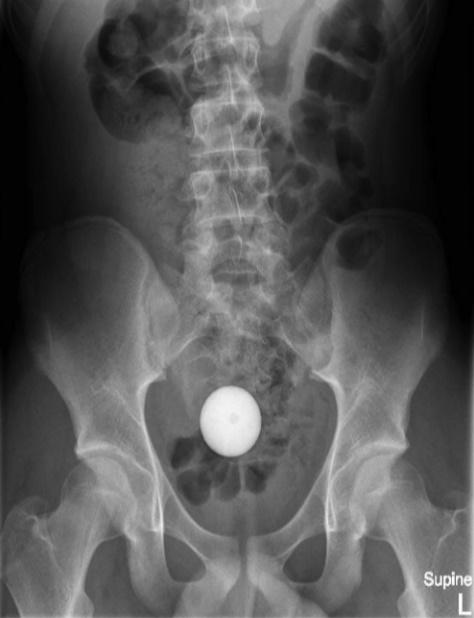

報告指出,這名少年將高爾夫球塞進自己的肛門,惟愈塞愈深,最後竟塞進腸道,雖然少年指無感到劇烈疼痛,但眼見自己已無法處理,只好向母親求助前往就醫。少年指出,雖然球球跑進體內,但他並沒有感受到劇烈疼痛感。X光顯示,一顆球體就在腹腔內。醫生決定先後使用醫療網、導管、吸引器等6種方法,希望將高爾夫球取出但失敗,折騰了2小時後,醫生亦要暫停休息。

醫生建議治療方法首選是瀉藥

24小時後,醫生再為少年照X光,但高爾夫球依然卡在腹腔,但少年的家屬不願意再讓少年接受入侵性治療,因此醫生轉開大量瀉藥,令少年最終「屙」出這顆高爾夫球,少年的腸道及胃道亦沒有受損,身體狀況一切正常,隨後就讓少年出院,但也警告他「不要再將東西塞入肛門直腸」。醫師除了在期刊上公開這起病例,亦在報告中強調,如果有異物進入病患體內,若病患的腸胃道正常的情況下,建議治療方法首選是瀉藥,以用最自然的方法將異物排出。